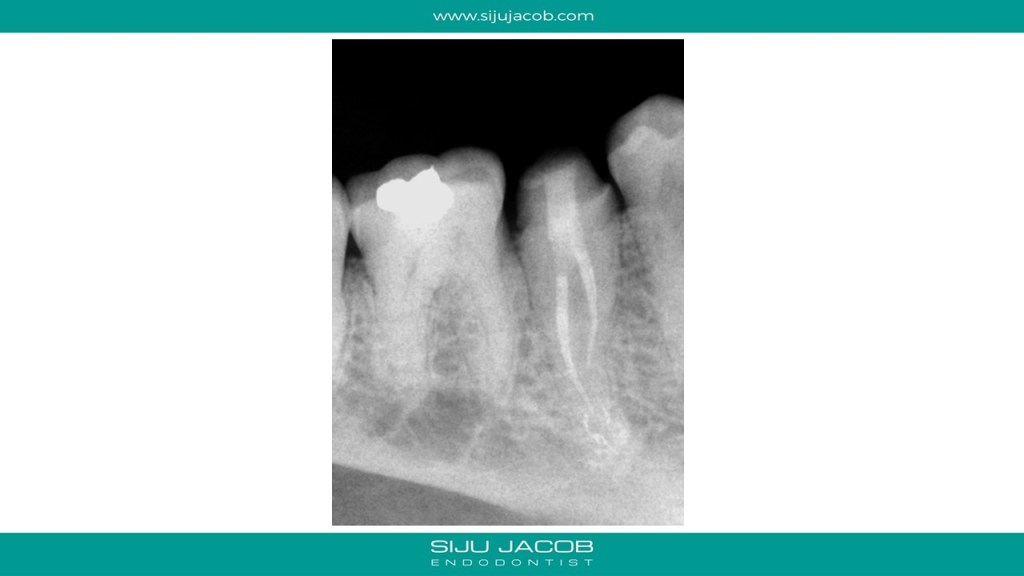

This is a routine clinical case of a mandibular premolar with 2 canals. Also attached is a small article I wrote in which I included this case and some other similar cases as well.